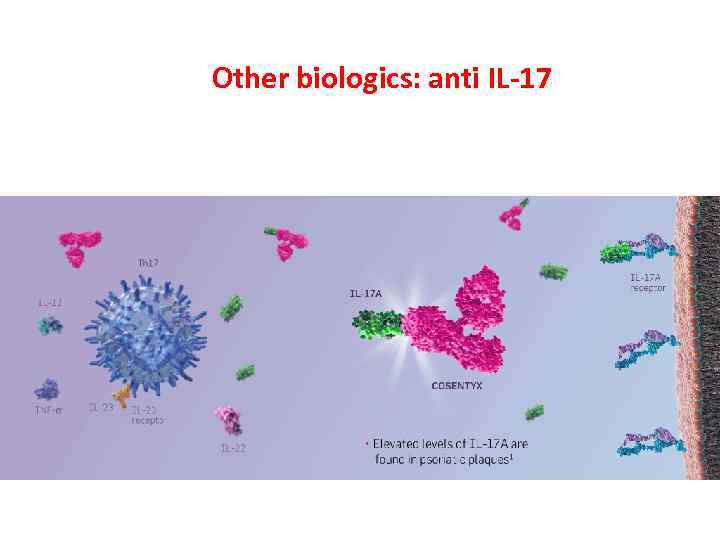

Other biologics: anti IL-17